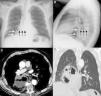

We report the case of a 73-year-old man, active smoker with no other significant medical history, who presented with central chest discomfort and weight loss. The first chest X-ray revealed a retrocardiac opacity with well-defined margins, containing an air-fluid level, initially suggesting a diagnosis of paraesophageal hiatal hernia, since part of the stomach was visualized in the left subphrenic region (Fig. 1A and B). Three weeks later, the patient consulted due to a self-limiting episode of hemoptysis; chest CT at that time showed an extensively cavitated pulmonary mass (Fig. 1C and D) with mediastinal infiltration. Squamous cell lung cancer was confirmed by fiberoptic bronchoscopy.

(A) Posteroanterior chest X-ray showing opacity in the right hemithorax (white arrows) containing an air-fluid level (black arrows). Note the gastric fundus (asterisk) protruding into the left subphrenic region. (B) Lateral chest X-ray confirming the retrocardiac location of the opacity (white arrows) with the air-fluid level (black arrows). (C) Axial CT image showing an extensively necrotic, cavitary mass (asterisk) in the paramediastinal region of the right lower lobe. Note the presence of an air-fluid level in the cavitated area. (D) Coronal CT image (pulmonary parenchymal window) confirming intrapulmonary lesion and preserved hemidiaphragms.